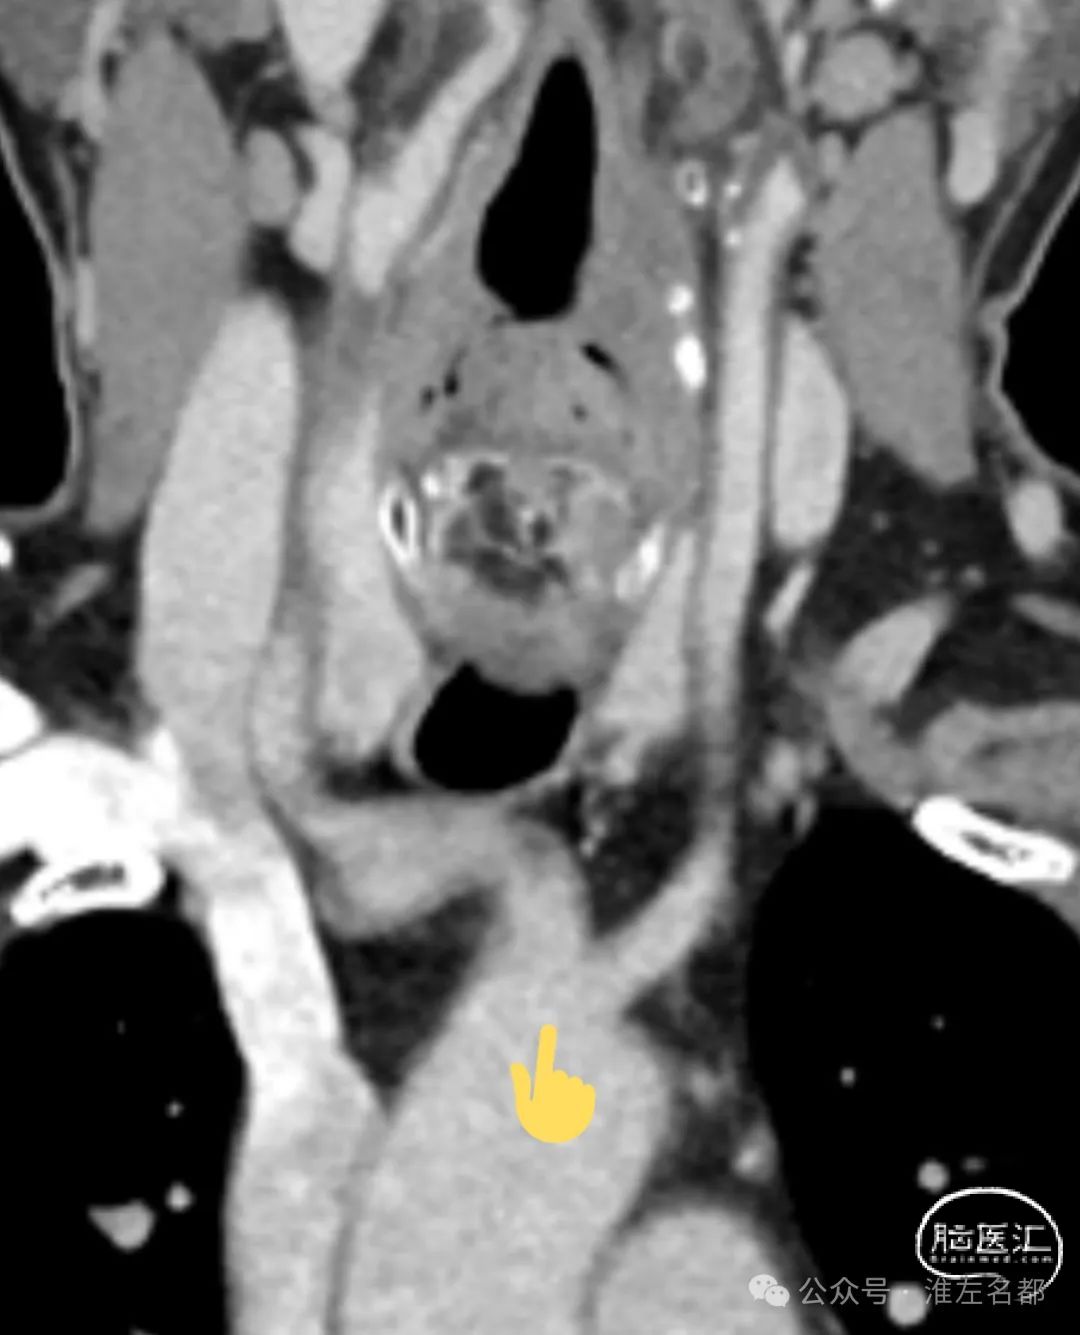

CTA:左ICA起始部重度狭窄,左CCA与无名动脉短共干,左CCA起始段走行明显向左,与主动脉弓呈显著锐角。